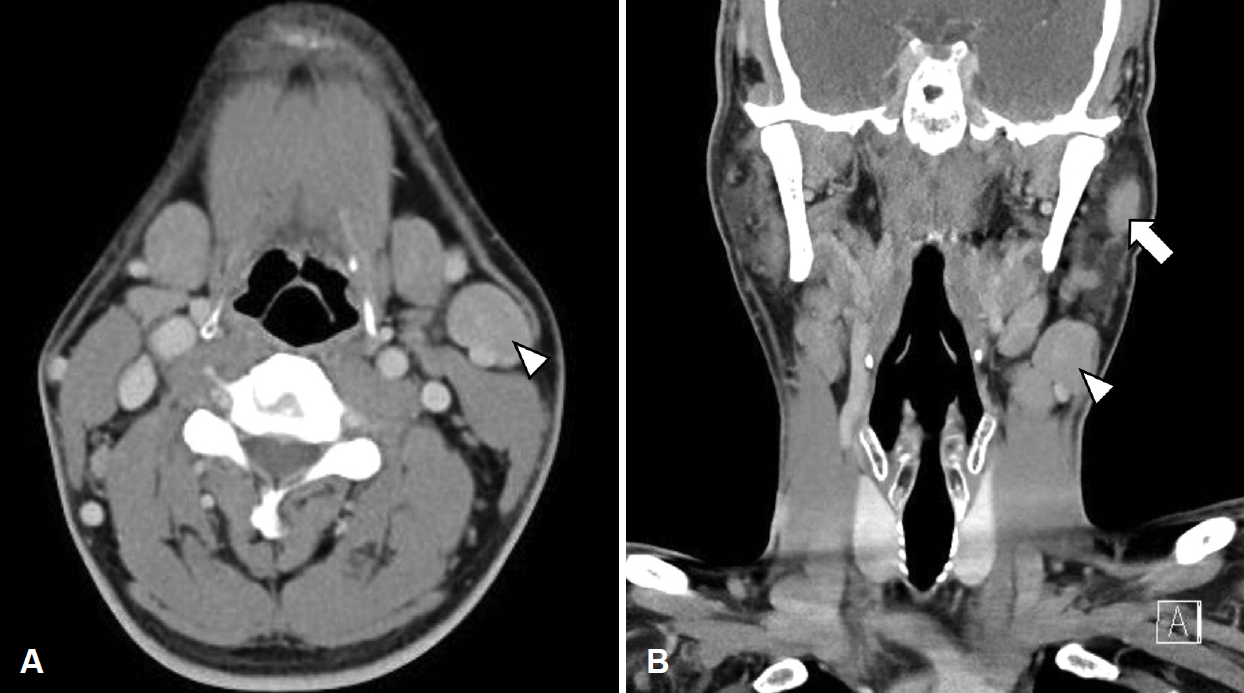

수술 후 1달 째 환자의 경부 종물 크기가 증가하여 경부 전산화단층촬영을 시행하였고, 양측 경부 구역 1b, 2, 3과 좌측 경부 5b, 이하선 내측에서 비괴사성 저음영의 림프절병증이 확인되었다(Fig. 4). 임파선 절제 생검에서도 비인두 종물의 조직소견과 같은 비건락성 육아종으로 사르코이드증에 가까운 소견을 보였으나 수술 후 40일 째에 비인두 조직 배양검사에서 결핵균의 배양이 확인되어 항결핵제 이소니아지드(isoniazid), 에탐부톨(ethambutol), 리팜핀(rifampin), 피라진아미드(pyrazinamide) 복용을 시작하였다. 흉부 단순촬영상에서 폐결핵 소견은 보이지 않았고, 환자가 알고 있는 결핵 병력은 없었으나 QuantiFERON-TB 검사상 양성소견이었다. 이때 흉부 전산화단층촬영을 권유하였으나 환자가 거부하여 수술 후 6개월째에 시행한 결과, 폐 우상엽과 좌하엽에서 경계가 뚜렷하지 않은 불분명하고 비특이적인 미세결절성 침윤이 확인되었다(Fig. 5). 결핵과 사르코이드증이 정확히 감별되지 않았으나 호흡기내과와 협진으로 비인두 조직 배양검사상 결핵균이 확인되었기에 결핵에 의한 병변으로 판단하여 치료하는 것이 적절하다고 생각하였다.

Neck CT findings 1 month after the operation. Axial (A) and coronal (B) image of neck CT showed multiple non-necrotic hypoattenuated lymphadenopathy in left intraparotid (arrow), both level 1b, 2 (arrowhead: left level 2), 3, and left level 5b.